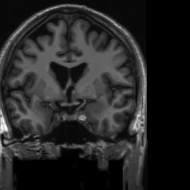

4.3 Medical Image Compressive Sensing

Medical image compressive sensing is an everlasting practical application in image reconstruction area. In this section we test the performance of the proposed ResGD-Net on compressive sensing reconstruction of brain MR images [3] (CS-MRI). In CS-MRI problem, the data fidelity term is , where , is a binary selection matrix representating the sampling trajectory, and is the discrete Fourier transform. We randomly pick images from the brain MRI datasets [3], then crop and keep the central part with less background. Then we at random divide the dataset to images for training and for testing. Among this section, we present the comparison results between ResGD-Net and ISTA-Net+ [33], where the latter one is a state-of-the-art method in tackling with CS-MRI problem. For fairness, both algorithms compared here are evaluated on the same dataset and metrics. Experiments are conducted across different sampling ratios , and of to show the generality. The study of ResGD-Net on different sampling ratios and various phase numbers is shown in Fig. 4. The PSNR comparison with ISTA-Net+ is shown in Table. 2. The result enhancement of the proposed ResGD-Net against ISTA-Net+ is remarkable across all sampling ratios even though we only use approximately many number of parameters than ISTA-Net+ [33].

In addition, we provide the visualization results of some selected MR images reconstructed by the state-of-the-art ISTA-Net+ [33] and our proposed ResGD-Net on compressive sensing (CS) ratio , and . The results are evaluated under metrics the Peak Signal-to-Noise Ratio (PSNR), the Structural Similarity (SSIM) and the Mean Squared Error (MSE). For better visualization, we rescale the pixel value by multiplying on the error maps (the second row of Figs. 5 - 7) when displaying.

PSNR: dB

SSIM:

MSE:

PSNR: dB

SSIM:

MSE:

PSNR: dB

SSIM:

MSE:

PSNR: dB

SSIM:

MSE:

PSNR: dB

SSIM:

MSE:

PSNR: dB

SSIM:

MSE: